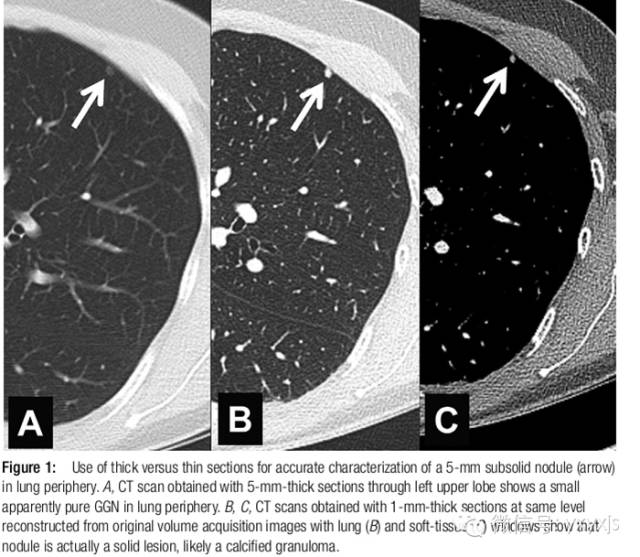

尤其是年老者,因为其在病理上代表AAH,少数为原位腺癌。扫描层厚必须为1mm以确定其是否为真正的GGO。